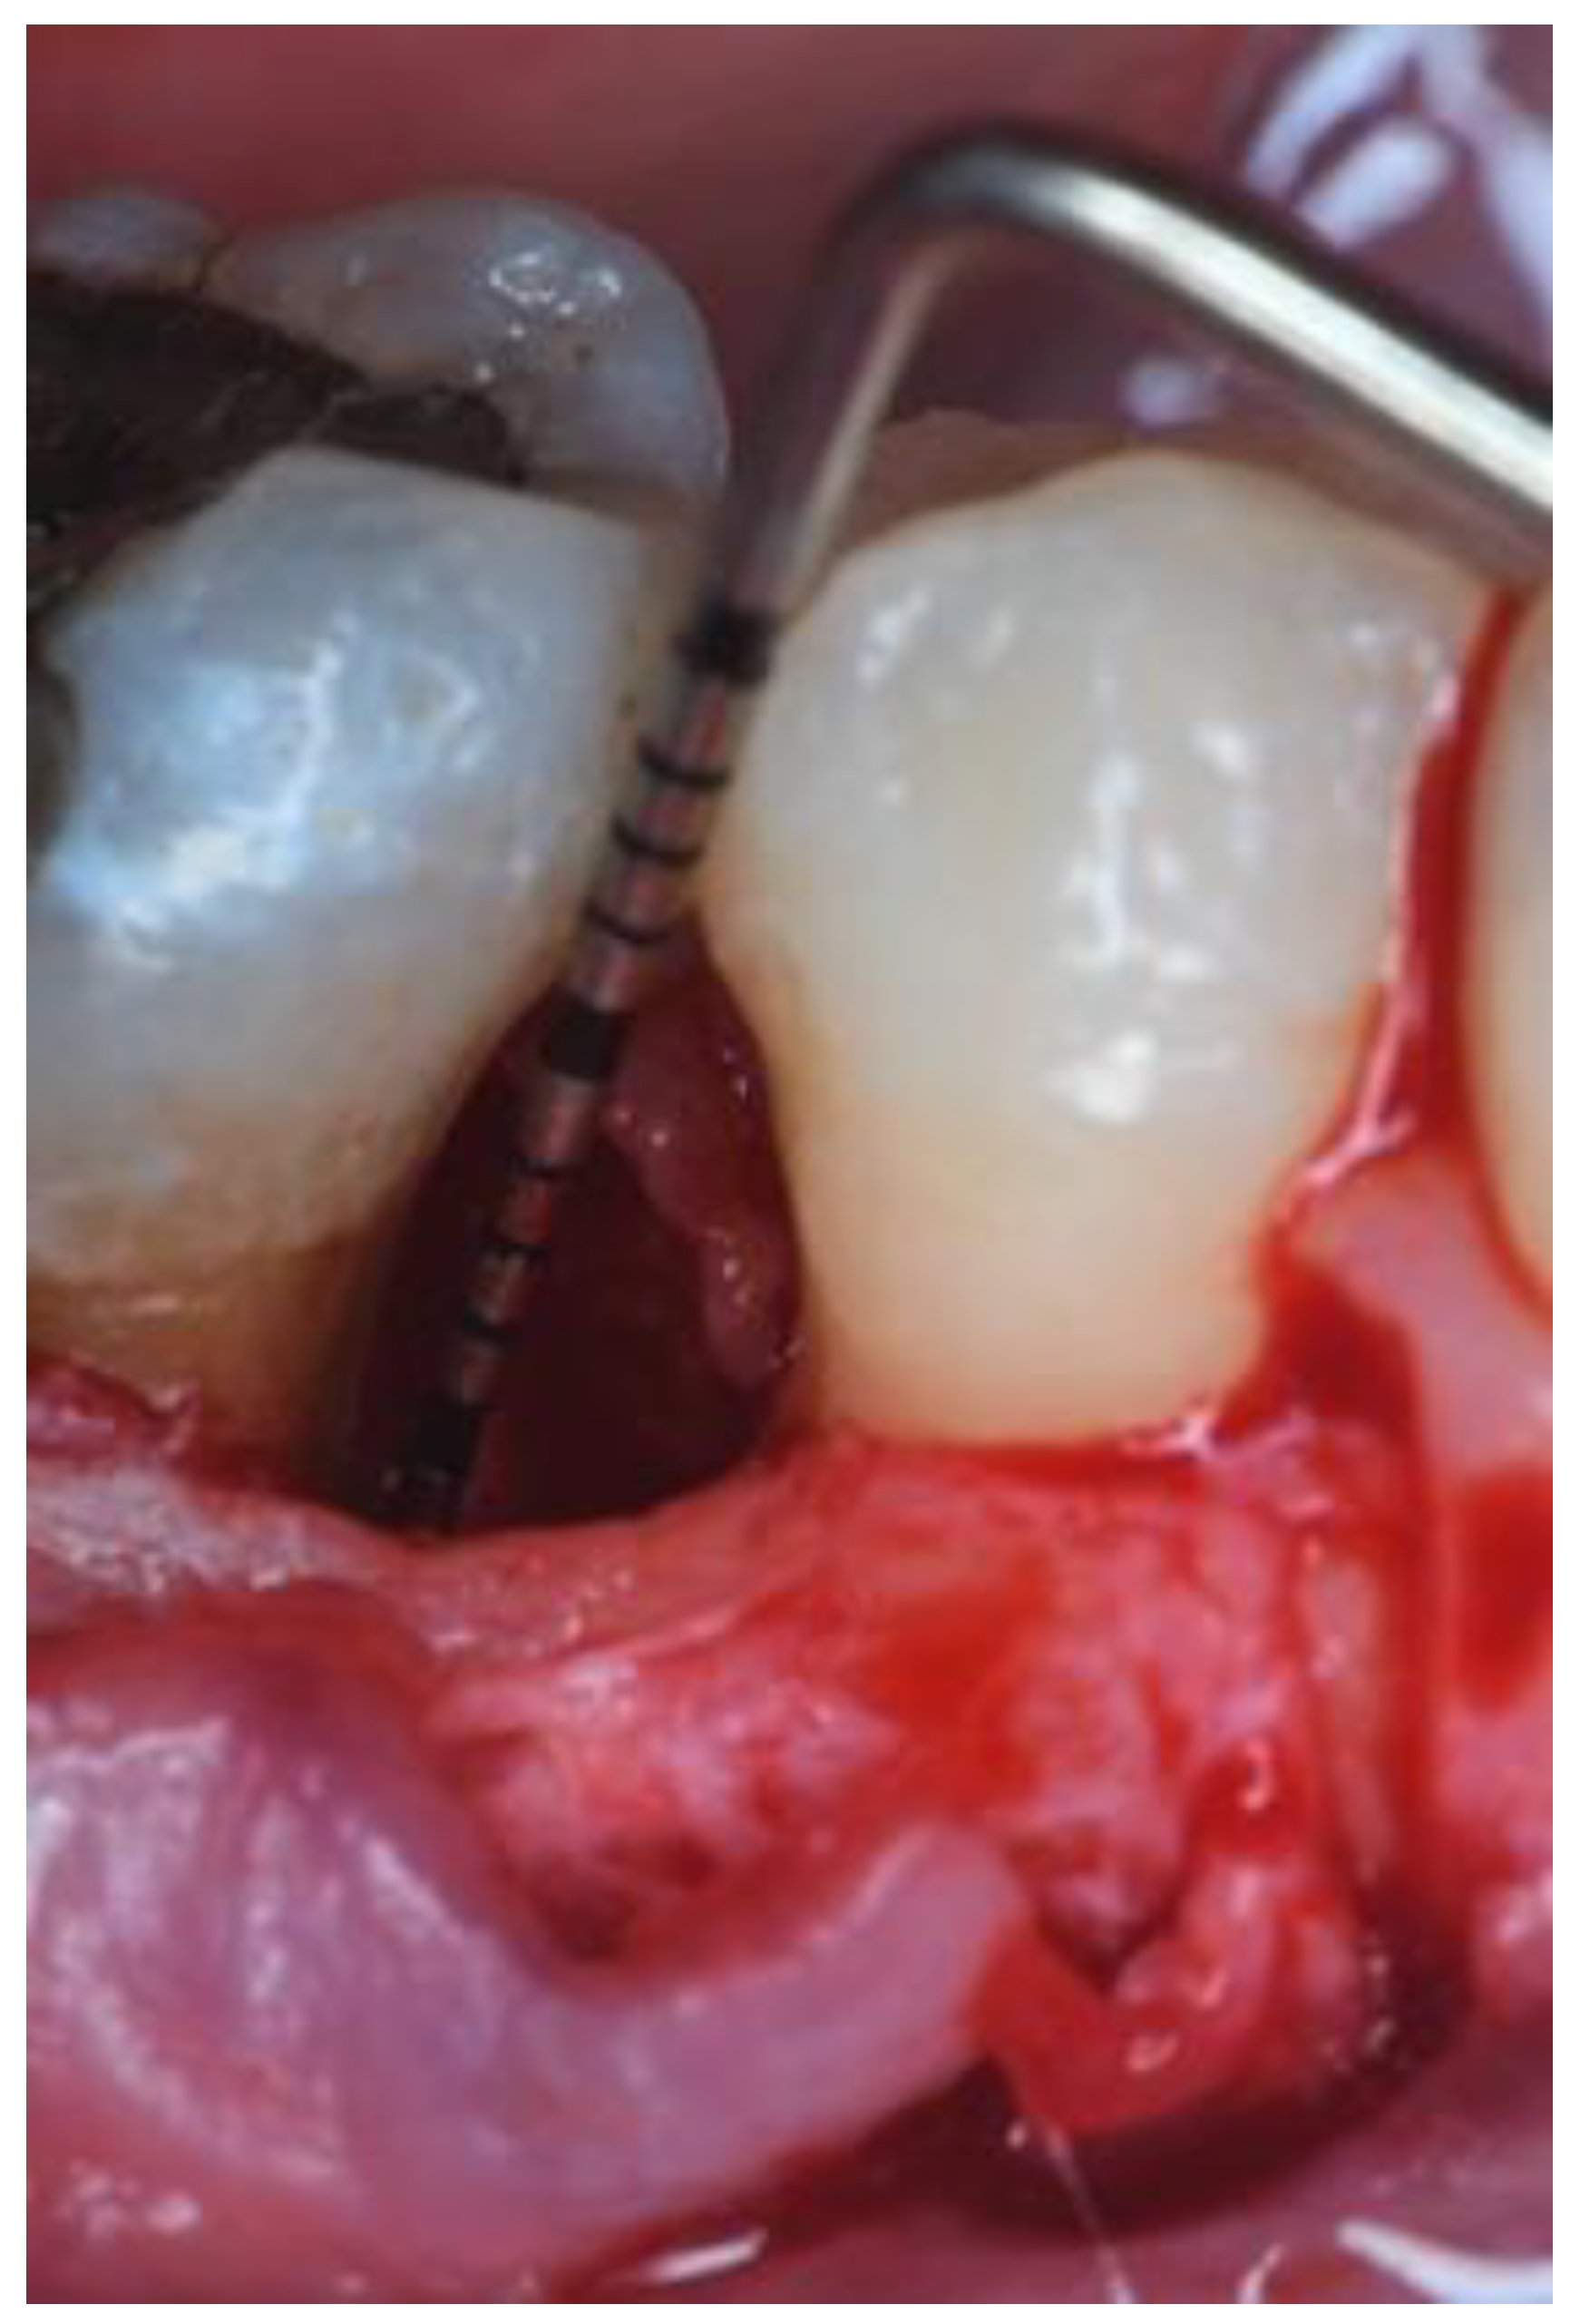

2.3. Therapeutic Intervention